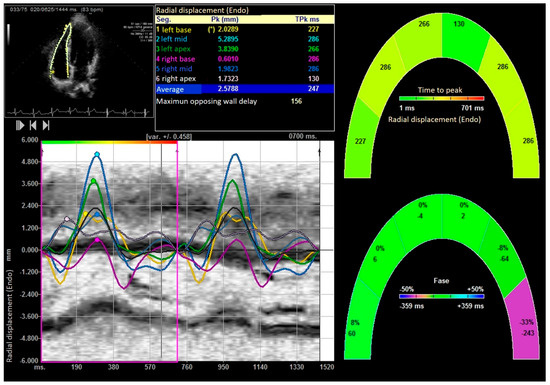

| Peak systolic radial velocities (cm/s) | 4.76 ± 0.48 | 1.76 ± 0.48 | 6.17 ± 1.35 | 0.0001 |

| E peak radial velocity (cm/s) | −1.75 ± 0.16 | −1.45 ± 0.54 | −2.21 ± 0.191 | 0.0001 |

| A peak radial velocity (cm/s) | −0.11 ± 0.12 | −0.09 ± 1.35 | −0.6 ± 0.22 | 0.0001 |

| Right ventricular Radial systolic displacement (mm) | 1.88 ± 1.78 | 1.33 ± 1.14 | 4.57 ± 0.96 | 0.0001 |

| Right ventricular Radial displacement delay (ms) | 182.14 ± 17.12 | 212.36 ± 18.96 | 124.32 ± 15.25 | 0.0001 |